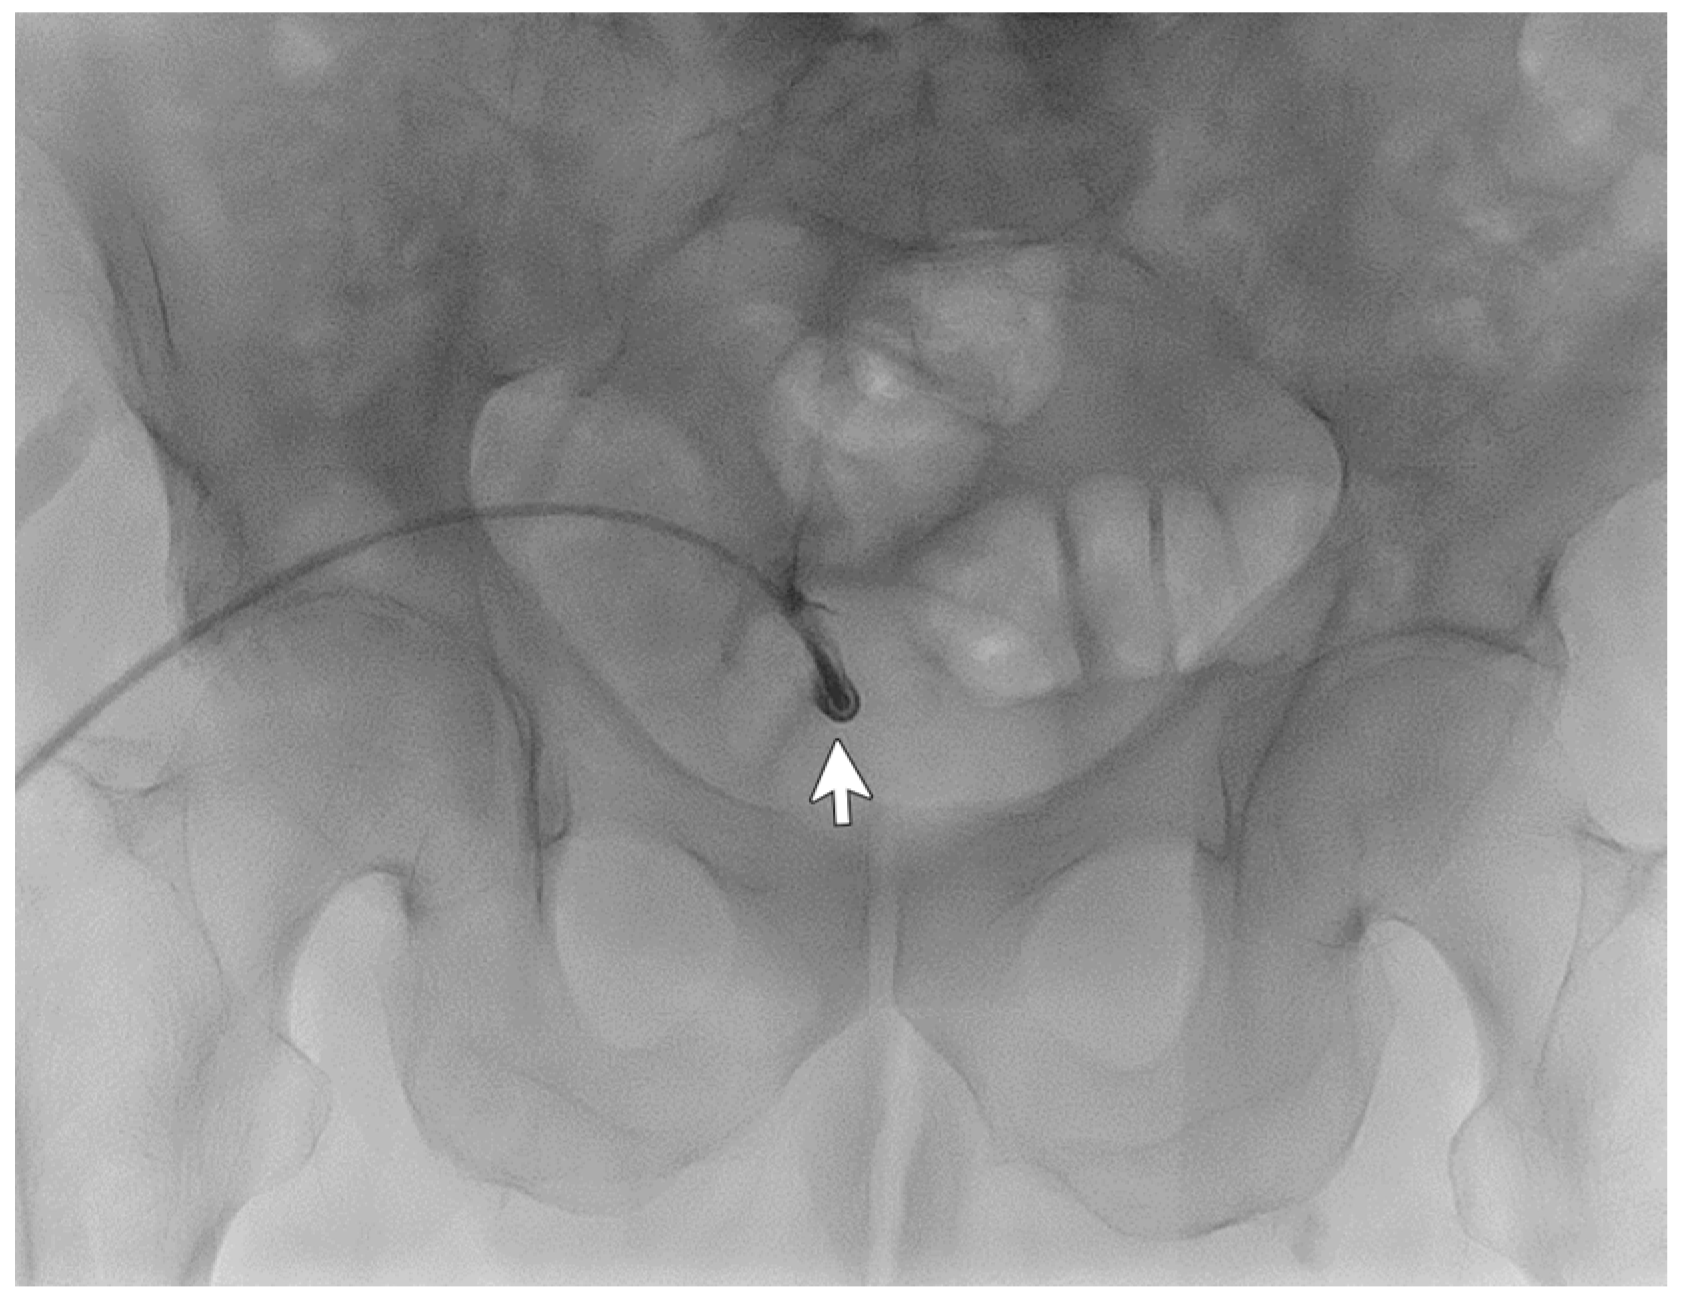

A 67-year-old male patient affected by Autosomal Dominant Tubulointerstitial Kidney Disease due to UMOD mutation (ADTKD-UMOD) in peritoneal dialysis for 15 months reported catheter malfunction since the start of peritoneal dialysis with many alarms occurring during the outflow phase of every APD cycle. The abdomen X-ray showed the correct position of the catheter tip, and laxatives did not help to reduce alarm frequency. Guidewire manipulation was successfully performed (Figure 3). The absence of spillage from the side holes made it suspicious for the presence of adhesions insinuated into the holes that may explain the drainage problems. Also, the use of the guidewire to force the movement of the catheter from its position may have helped to debride the catheter from adhesions. The patient did not report pain or any other complication of the procedure and could re-take peritoneal dialysis right afterward. One month after the procedure, the patient could still effectively perform peritoneal dialysis.

Figure 3. Catheterography showing no spillage of contrast medium from the side holes.